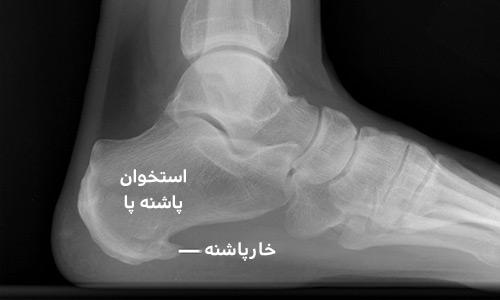

خارپاشنه به رسوب کلسیم در پاشنه پا که باعث برآمدگی استخوان در قسمت زیرین استخوان پاشنه می‌شود خارپاشنه می‌گویند. خار پاشنه خود را به صورت دردي آزاردهنده، سوراخ كننده و عمقي دركف پا نزديك به پاشنه نشان مي دهد .درد پاشنه در صورت عدم درمان باعث لنگش شده و راه رفتن طبيعي را تحت تاثير قرار خواهد داد. همين امر باعث وارد آمدن فشارهاي نامتعارف به زانو، مفصل و ران و كمر مي شود كه مي تواند در اين نواحي درد و عوارض دیگر ایجاد كند. این عارضه در عکس برداری اشعه ایکس خود را به صورت یک زائده استخوانی نشان می دهد که جنس این زائده از آهک یا کلسیم است. کرم خار پاشنه کرویا درمان این بیماری است. نحوه اثر کرم ترک پا وخارپاشنه کرویا : مواد موثره موجود درکرم باعث گرم شدن موضعی شده و گردش خون موضعی را زیاد می‌کند و تغذیه بافت اطراف موضع را بهبود می‌بخشد که تاثیر چشمگیری در بهبود ترک های عمقی کف پا و از بین رفتن آن دارد .همچنین سبب ترمیم رباط کف پاشنه پا می گردد. این کرم با جذب از کف پا، با نرم کردن و نهایتا حل کردن توده های سخت آهکی– کلسیمی و اثرات ثابت شده ضد التهابی باعث بهبود و برطرف شدن عارضه خار پاشنه می‌گردد. روش های مرسوم خار پاشنه بیشتر بر مبنای استفاده از هورمون ها و داروهای ضد التهاب و درد است که عموما در ابتدا اثرات تسکینی خوبی ظاهر میکنند ولی پس از مدتی عملکرد آنها ضعیف شده و یا نیاز به مصرف دوز بیشتر دارد و حتی ممکن است کاملا بی اثر گردند. این محصول 100% ارگانیک و فاقد هر نوع ترکیب شیمیایی و مصنوعی است و هیچ گونه عوارض جانبی ندارد جهت دریافت نتیجه بهتر توصیه می شود استفاده از کرم تا بهبود کامل ادامه داشته باشد ( 2 عدد کرم) کاربرد این محصول گیاهی موارد زیر است: . بهبود ترک های عمیق پاشنه پا . بهبود سریع خار پاشنه . رفع التهاب در رباط کف پا (پلانتار فاشیا) . تسکین درد و التهاب با منشاء نا معلوم کف و پاشنه پا